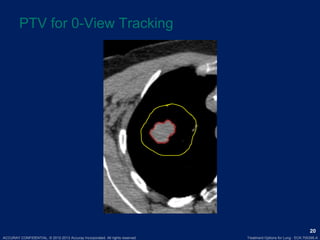

PTV for 0-View Tracking

ACCURAY CONFIDENTIAL. ©2012-2013 Accuray Incorporated. All rights reserved. Treatment Options for Lung · ECK.700395.A 20 PTV for 0-View Tracking